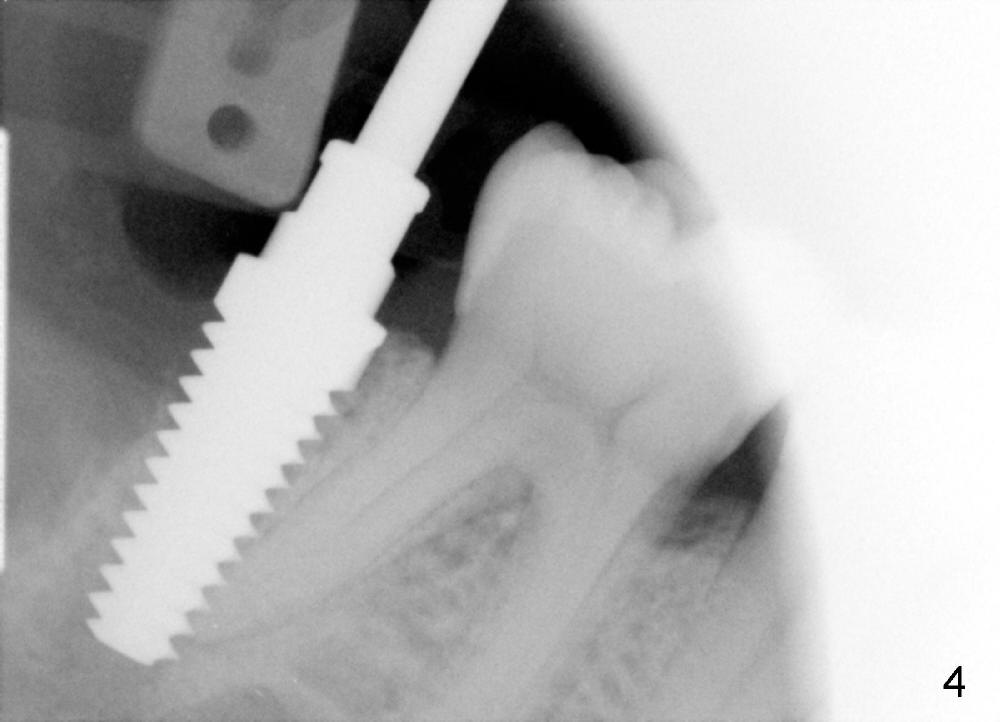

A: after obtaining verbal and written sx consent, Mepivacaine 54 mg, Xylo 34 mg, Septo 68, Epi 34 mcg infiltration, separated gingiva with periotome, pt had pain, Marcaine 9 mg, Xylo 34 mg, Epi 26 mcg infiltration and intraligamental injection, routine ext with forceps, curettage with serrated curette, lot of granulation tissue, until the bottom of the socket, close to presumptive inferior alveolar canal, tissue apparently running mesiodistally, easily removed without active hemorrhage, distal root has abundant calculus, distal socket apparently too large for implantation, copious irrigation, placed Clindamycin gauze x3, mesial socket flat (B-L width is much bigger than M-L one), inserted D1,2 spreader and D2 socket formers with difficulty, handles contact #30 distal crown, inserted RT 2,3,4 and tapered osteotomes 5x18 and 6x18 mm, trying to move the septum distally with much help, inserted 4.5x20 mm tap at 17 mm depth, stable, PA taken: tap close to #30 distal root, approaching IAN (Fig.3), changed to 5x17 tap at 14 mm without stability, when 6x17 tam is inserted at 14 mm, it is stable, PA taken: tap very close to #30 distal root (Fig.4), removed the tap (mesial wall of the mesial socket: no obvious perforation with distal root of #30) and droppd it  into in the distal socket, PA: tap tip overlaps IAN canal (Fig.5), discussed possible nerve injury and touching neighboring root, pt agreed to abort implant placement and place bone graft. placed collagen plug (CollaForm-Plug, Absorbable Collagen Wound DRef CFP1020_5, Lot CFP1020_1301)) in the bottom of the socket (to make room for nerve regeneration), inserted ~.6 cc CANCELL Oss (Mineralized Cancellous Human Allograft, distributed by Implandent LTD, .850-1 mm, 03-0494763/03-0494749, Product Code 06412201, mixed with .3 mg Osteogen (300-400 micron, Osteoconductive Synthetic Bioactive Resorbable Graft, Impladent LTD) into sockets, placed another collagen plug on the top of bone graft, 4-0 chromic gut suture (figure 8 and 1 interrupted), perio dressing, hemostatic. Pt was doing well. POI (oral) and extra gauze given. Continue Amoxicillin, Chlorhexidine, Medrol and Norco, Vitamin B complex recommended